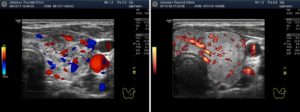

- Фиброаденома (доброкачественная опухоль из соединительной и железистой ткани) визуализируется в виде округлого или овального образования, с четкими контурами. Имеет однородную структуру, пониженную или несколько повышенную эхогенность; характерен периферический тип кровотока (когда сосуды при ЦДК окружают опухоль).

- Рак молочных желез. Это могут быть единичные или множественные образования различных размеров, неправильной формы, с бугристыми контурами, неоднородной структуры. Нередко в них выявляются кальцификаты (мелкие гиперэхогенные точечки) и смешанный тип кровотока. Зачастую обнаруживаются измененные лимфоузлы.

Основным достижением ЦДК в диагностике опухолевых процессов является визуализация и оценка кровотока новообразованных сосудов опухоли, которые имеют свои характерные особенности. Система васкуляризации опухоли представлена множеством мелких, очень тонких, аномальных по форме и расположению сосудов, хаотично разбросанных в пределах опухолевых тканей.

Кровоток в этих сосудах характеризуется крайне низким сосудистым сопротивлением, высокой скоростью и разнообразным направлением.

Кровоток в доброкачественных опухолях имеет иной характер. Сосуды, участвующие в васкуляризации доброкачественных образований матки и яичников, являются непосредственным продолжением терминальных ветвей маточных и яичниковых артерий.

По мнению большинства авторов периферическая, с единичными сосудами, васкуляризация опухоли должна ассоциироваться с доброкачественностью, а наличие множественных сосудов в центральной части, на перегородках и в папиллярных разрастаниях является признаком злокачественноcти.

При цветовой допплерографии регистрируются единичные цветовые сигналы от сосудов, расположенных в капсуле образования, со средним уровнем индекса резистентности (IR min = 0,57+0,09 и 0,54+0,09).

Цветовая допплерография регистририрует “бедный” периферический кровоток в сосудах новобразования со средним уровнем резистентности (IR min = 0,59+0,03).

Цветовая допплерография позволяет выявить неоваскуляризацию опухоли: множественные цветовые сигналы от сосудов в пристеночных разрастаниях, на перегородках и в капсуле опухоли с низким уровнем резистентности (IR min – 0,40+0,07).